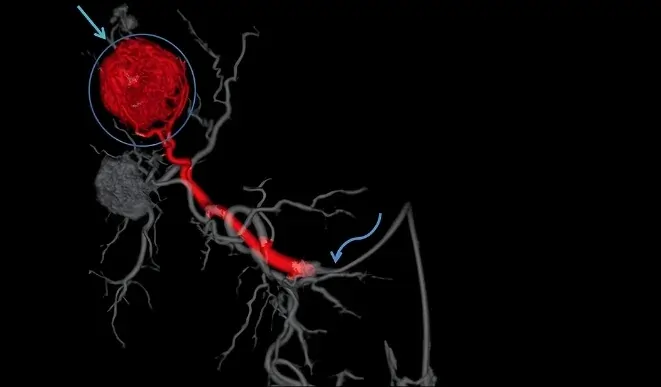

Trans-Arterial Chemoembolization (TACE) is a minimally invasive, targeted cancer treatment primarily used for liver tumors. It delivers chemotherapy directly to the tumor while simultaneously blocking its blood supply, maximizing effectiveness and minimizing damage to healthy tissue. TACE is performed using advanced imaging guidance and personalized treatment planning to ensure safe, precise, and effective tumor control.

TACE is an image-guided interventional oncology procedure in which chemotherapy drugs are delivered directly into the artery supplying the tumor. Once the drug is delivered, embolic agents are used to block the blood flow to the tumor, trapping the chemotherapy at the target site. This dual action helps shrink or control tumor growth while reducing systemic side effects compared to conventional chemotherapy.